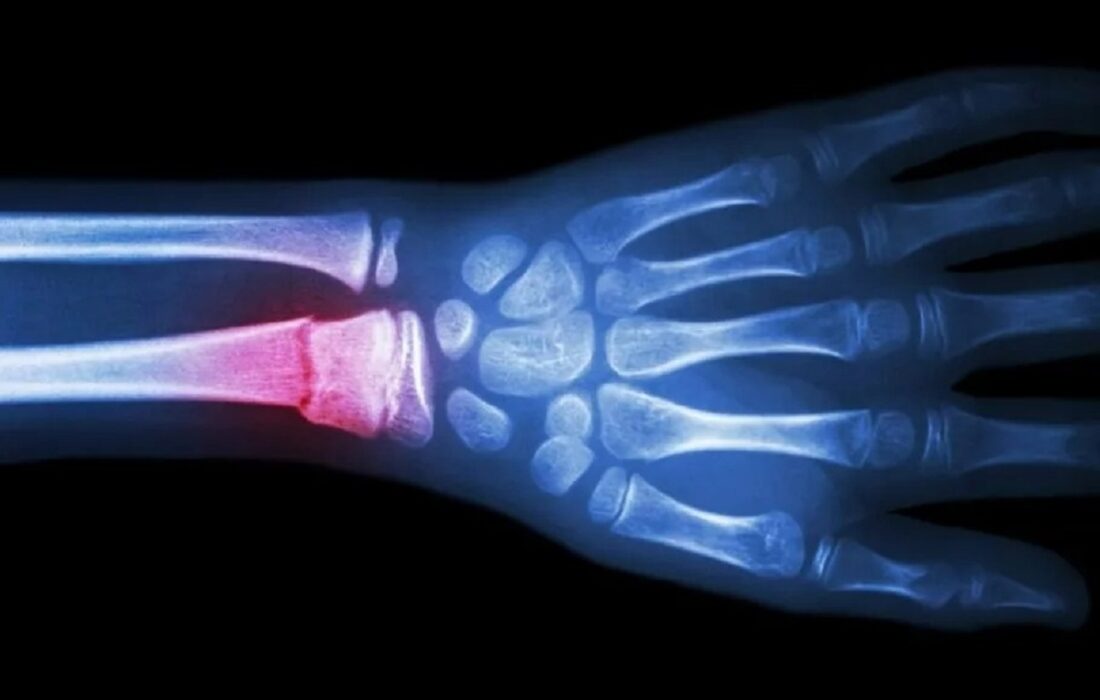

به گزارش اخبار جهان به نقل از دیجیاتو، محققان دانشگاه سونگکیونکوان کره جنوبی و دانشگاهی در ایالات متحده، گامی انقلابی در زمینه جراحی ترمیم استخوان برداشتهاند. آنها دستگاهی شبیه به تفنگ چسب ابداع کردهاند که قادر به چاپ سهبعدی پیوندهای استخوانی زیستتخریبپذیر بهصورت مستقیم در محل شکستگی یا نقص استخوانی در حین عمل جراحی است. این پیشرفت میتواند تحولی عظیم در جراحی ارتوپدی ایجاد کند و به ویژه در ساخت ایمپلنتهای کاملاً شخصیسازیشده و کاهش خطر عفونتهای پس از عمل نقش بسزایی داشته باشد.